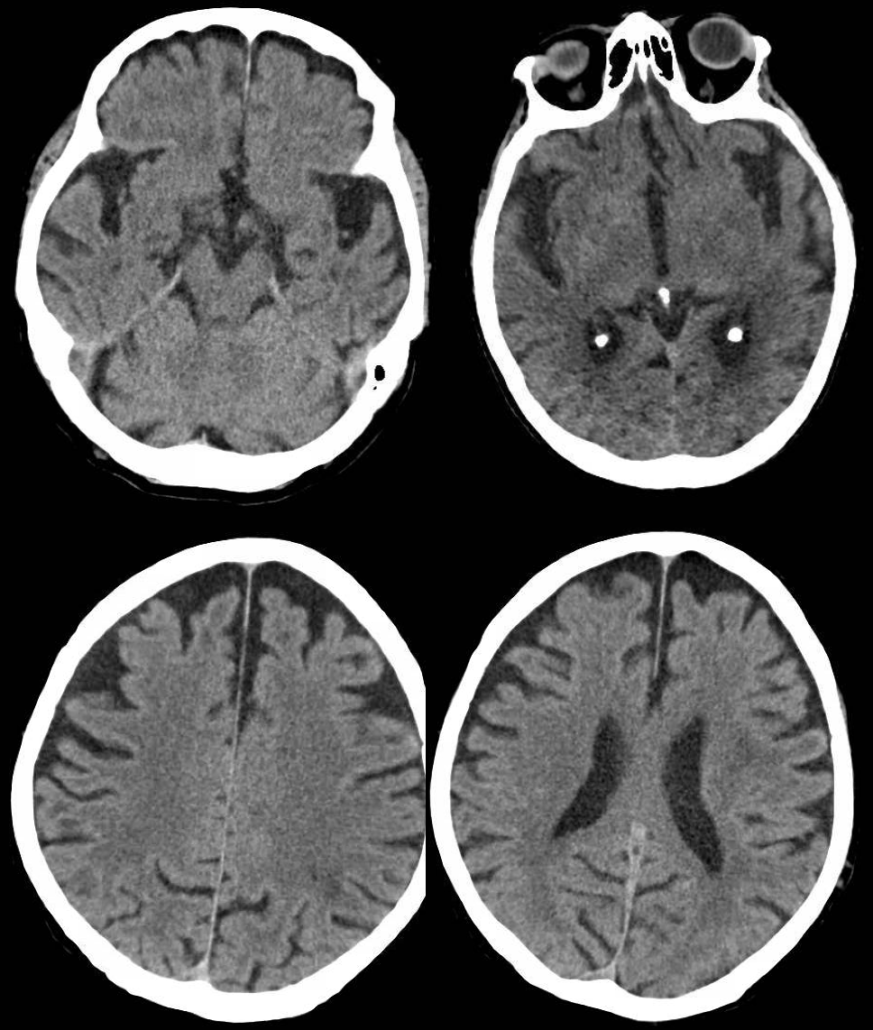

El número de “demencias” es elevado. La más conocida y frecuente es la enfermedad de Alzheimer (antigua “demencia senil”), que suele comenzar con fallos en la memoria reciente, y que afecta sobre todo a las personas de mayor edad, pero que puede presentarse en edades tempranas, incluso por debajo de los 50 años. La segunda en frecuencia es la “demencia vascular”, que se debe a lesiones vasculares en el cerebro (infartos o hemorragias) y puede afectar a diferentes facultades según dónde se produzcan estas lesiones, por lo que prevenir su aparición o progresión es primordial para una adecuada salud cognitiva. Otros tipos de “demencia”, como la “demencia fronto-temporal”, afectan más a la conducta y comportamiento de los pacientes, generando dificultades para la convivencia familiar y social. En todos estos casos, lo más importante es detectar el problema lo antes posible, para alcanzar un diagnóstico temprano y aplicar las medidas preventivas y terapéuticas existentes para su control o, cuanto menos, enlentecer el curso natural de la enfermedad, según su causa.

La mayor parte de estos problemas no disponen de un test diagnóstico directo, es decir, de una prueba en clave de “positivo o negativo” que permita confirmar o excluir con ella de forma absoluta que se padece la enfermedad. Sólo la evaluación directa por un neurólogo, en muchos casos apoyado también por la evaluación de un neuropsicólogo, y por la interpretación de las pruebas complementarias oportunas, nos permite alcanzar un diagnóstico de probabilidad fiable con el que tomar las medidas oportunas en pro de mejorar en lo posible su pronóstico.